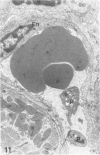

In male BALB/c mice aged 5-6 weeks inoculated three times at intervals of 15 days with 1 X 10(7) epimastigote forms of the PF strain of Trypanosoma cruzi and challenged 30 days after the last inoculation with 2 X 10(4) trypomastigote forms of the Colombia strain of T cruzi (the mice were sacrificed 80-100 days after the challenge) a cardiomyopathy very similar to that observed in the chronic phase of Chagas' disease in man develops. The cardiac syndrome is characterized grossly by cardiomegaly with hypertrophy, dilatation of ventricular chambers, and thinning of the apex of the left ventricle (apical aneurysm) and microscopically by focal areas of myocytolytic necrosis and myocardial degeneration with an inflammatory response composed of mononuclear cells (predominantly macrophages and a few lymphocytes) with concurrent interstitial fibrosis and occasional myofibers containing pseudocysts. In addition, aggregated platelets and occlusive thrombi were found in small epicardial and intramyocardial vessels of infected mice as compared with controls. The potential role of intravascular platelet aggregation in the causation of focal myocardial necrosis and degeneration and apical aneurysm in experimental T cruzi cardiomyopathy in BALB/c mice is discussed.